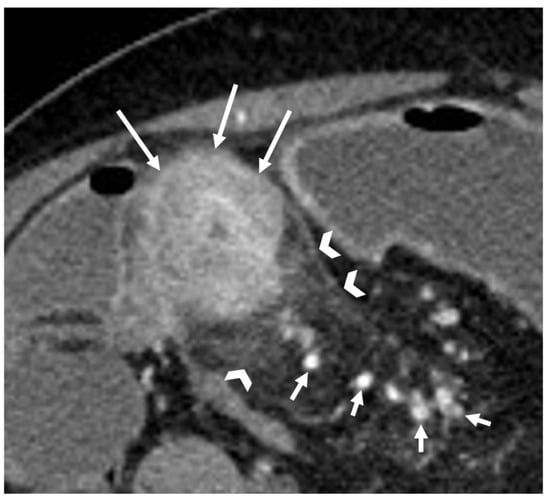

- A normal bowel loop caliber ranges between 2 and 2.5 cm. A bowel lumen is dilated when it has a maximum diameter greater than 2.5–3 cm. The dilation is mild when the upstream lumen is dilated up to 4 cm and severe when it is more than 4 cm (Figure 3) [24]. Pre-stenotic bowel dilatation should always be checked, as it is a sign related to bowel obstruction. Moderate to severe stenosis was determined via double-contrast imaging (conventional barium study) with a sufficient amount of injected air, and stenosis was defined as stenosis in which the lumen was less than one half that of neighboring healthy intestine [25].